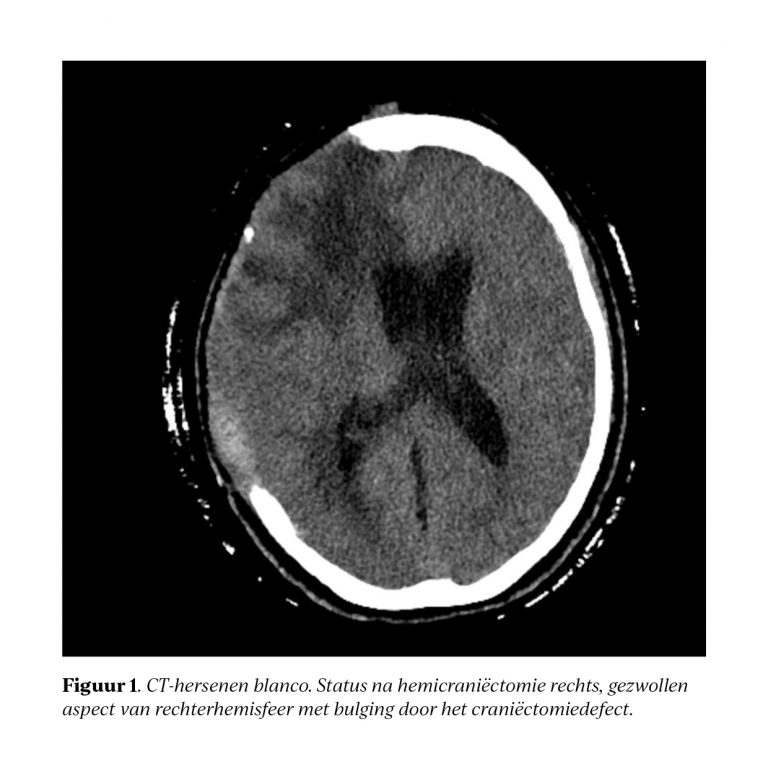

Stagnerende revalidatie na craniëctomie: denk aan het post-trepanatiesyndroom